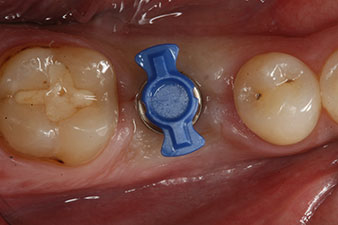

SmartPeg

Figura 4: Poste de medición atornillado SmartPeg para determinar el cociente de estabilidad del implante con el módulo Osstell ISQ de W&H.

El torque en el momento de la carga mecánica fue de 43 Ncm. Asimismo, después de atornillar un poste de medición especial adaptado al sistema de implante (SmartPeg), el valor ISQ se determinó con la sonda del módulo Osstell ISQ de W&H.

Este módulo Osstell ISQ que se encuentra disponible como accesorio para la unidad Implantmed de W&H y se acopla al motor de implantes (véase figura 11). El valor ISQ adimensional fue de 64 justo en el momento de la inserción en la dirección bucovestibular y de 68 en la dirección mesiodistal (valor máximo = 100).